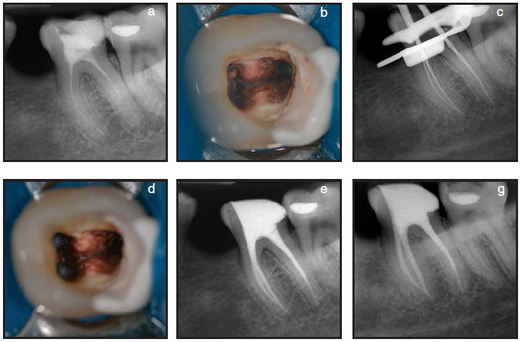

Пульпит- в процессе глубокого кариеса, продукты жизнедеятельности бактерий и распада проникают в пульпу (нерв), вызывая восспаление нерва. При пульпити необходимо эндодонтическое лечение и пломбирование корневых каналов зуба.

Материал для пломбирование каналов зуба индивидуален. Зависит от анатомии зуба, количество корней зубов, кривизны каналов зуба.